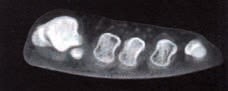

Aber nicht nur gebrauchte Schuhe zeigen eine Hohllegung des Ballenbereiches, sondern auch neue Schuhe sind im Ballenbereich schon primär gerundet. So ergab eine computertomografische Untersuchung neuer unbenutzter Schuhe 4, dass bei allen Exemplaren der Ballenbereich in seiner Mitte tiefergelegt ist (Abb. 5).